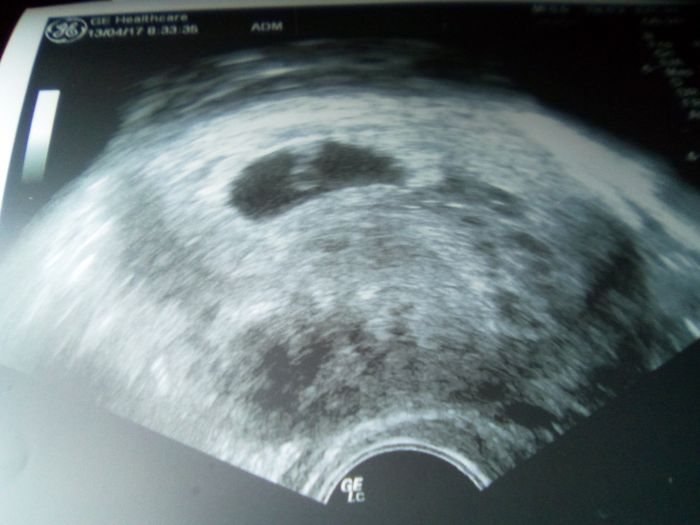

já jsem se dřív na net nedostala, dnes na utrazvuku viděla paní doktorka plod i pulzující srdíčko, odpovídá 6+2, dostala jsem i fotečku :-)